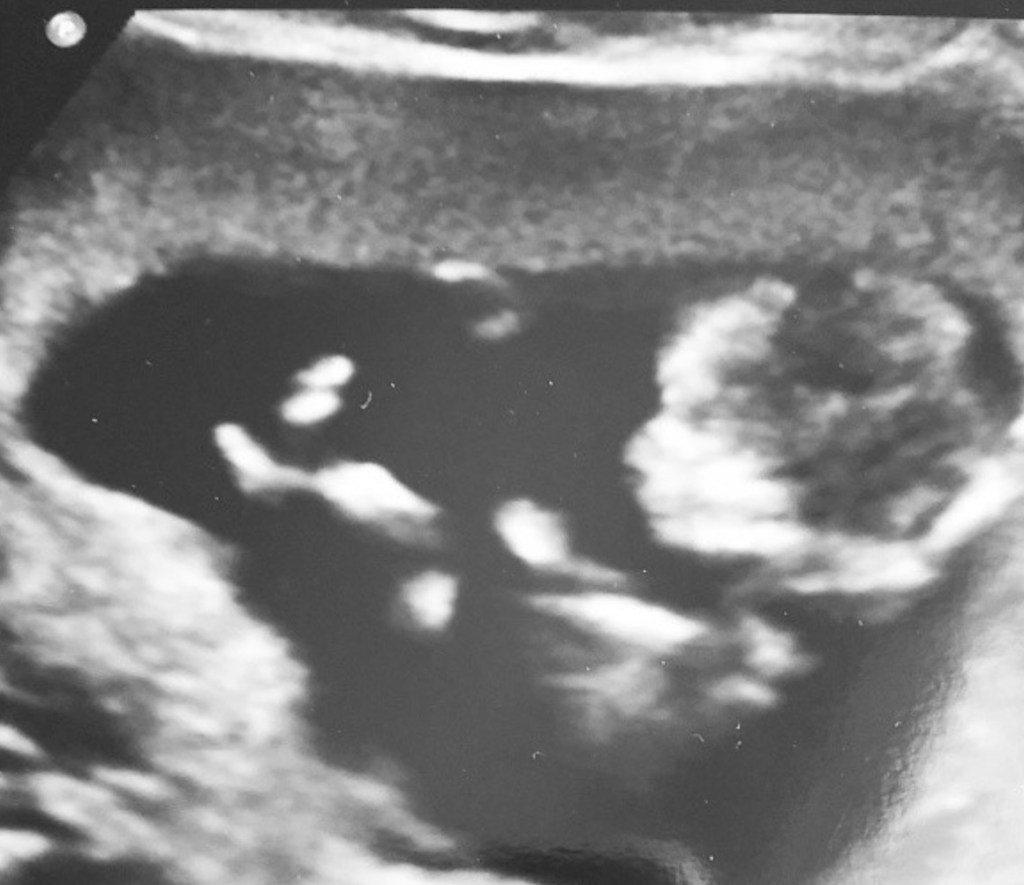

Being twenty one and 13 weeks pregnant, I went straight to the hospital to get checked out. I was by myself and with a social worker, as I wasn’t expecting the words that were about to come out of the ultrasound technician’s mouth.

Blood tests were done, and I was put on a drip, later to be told I had a very severe kidney infection, among other things, which resulted in my miscarriage.